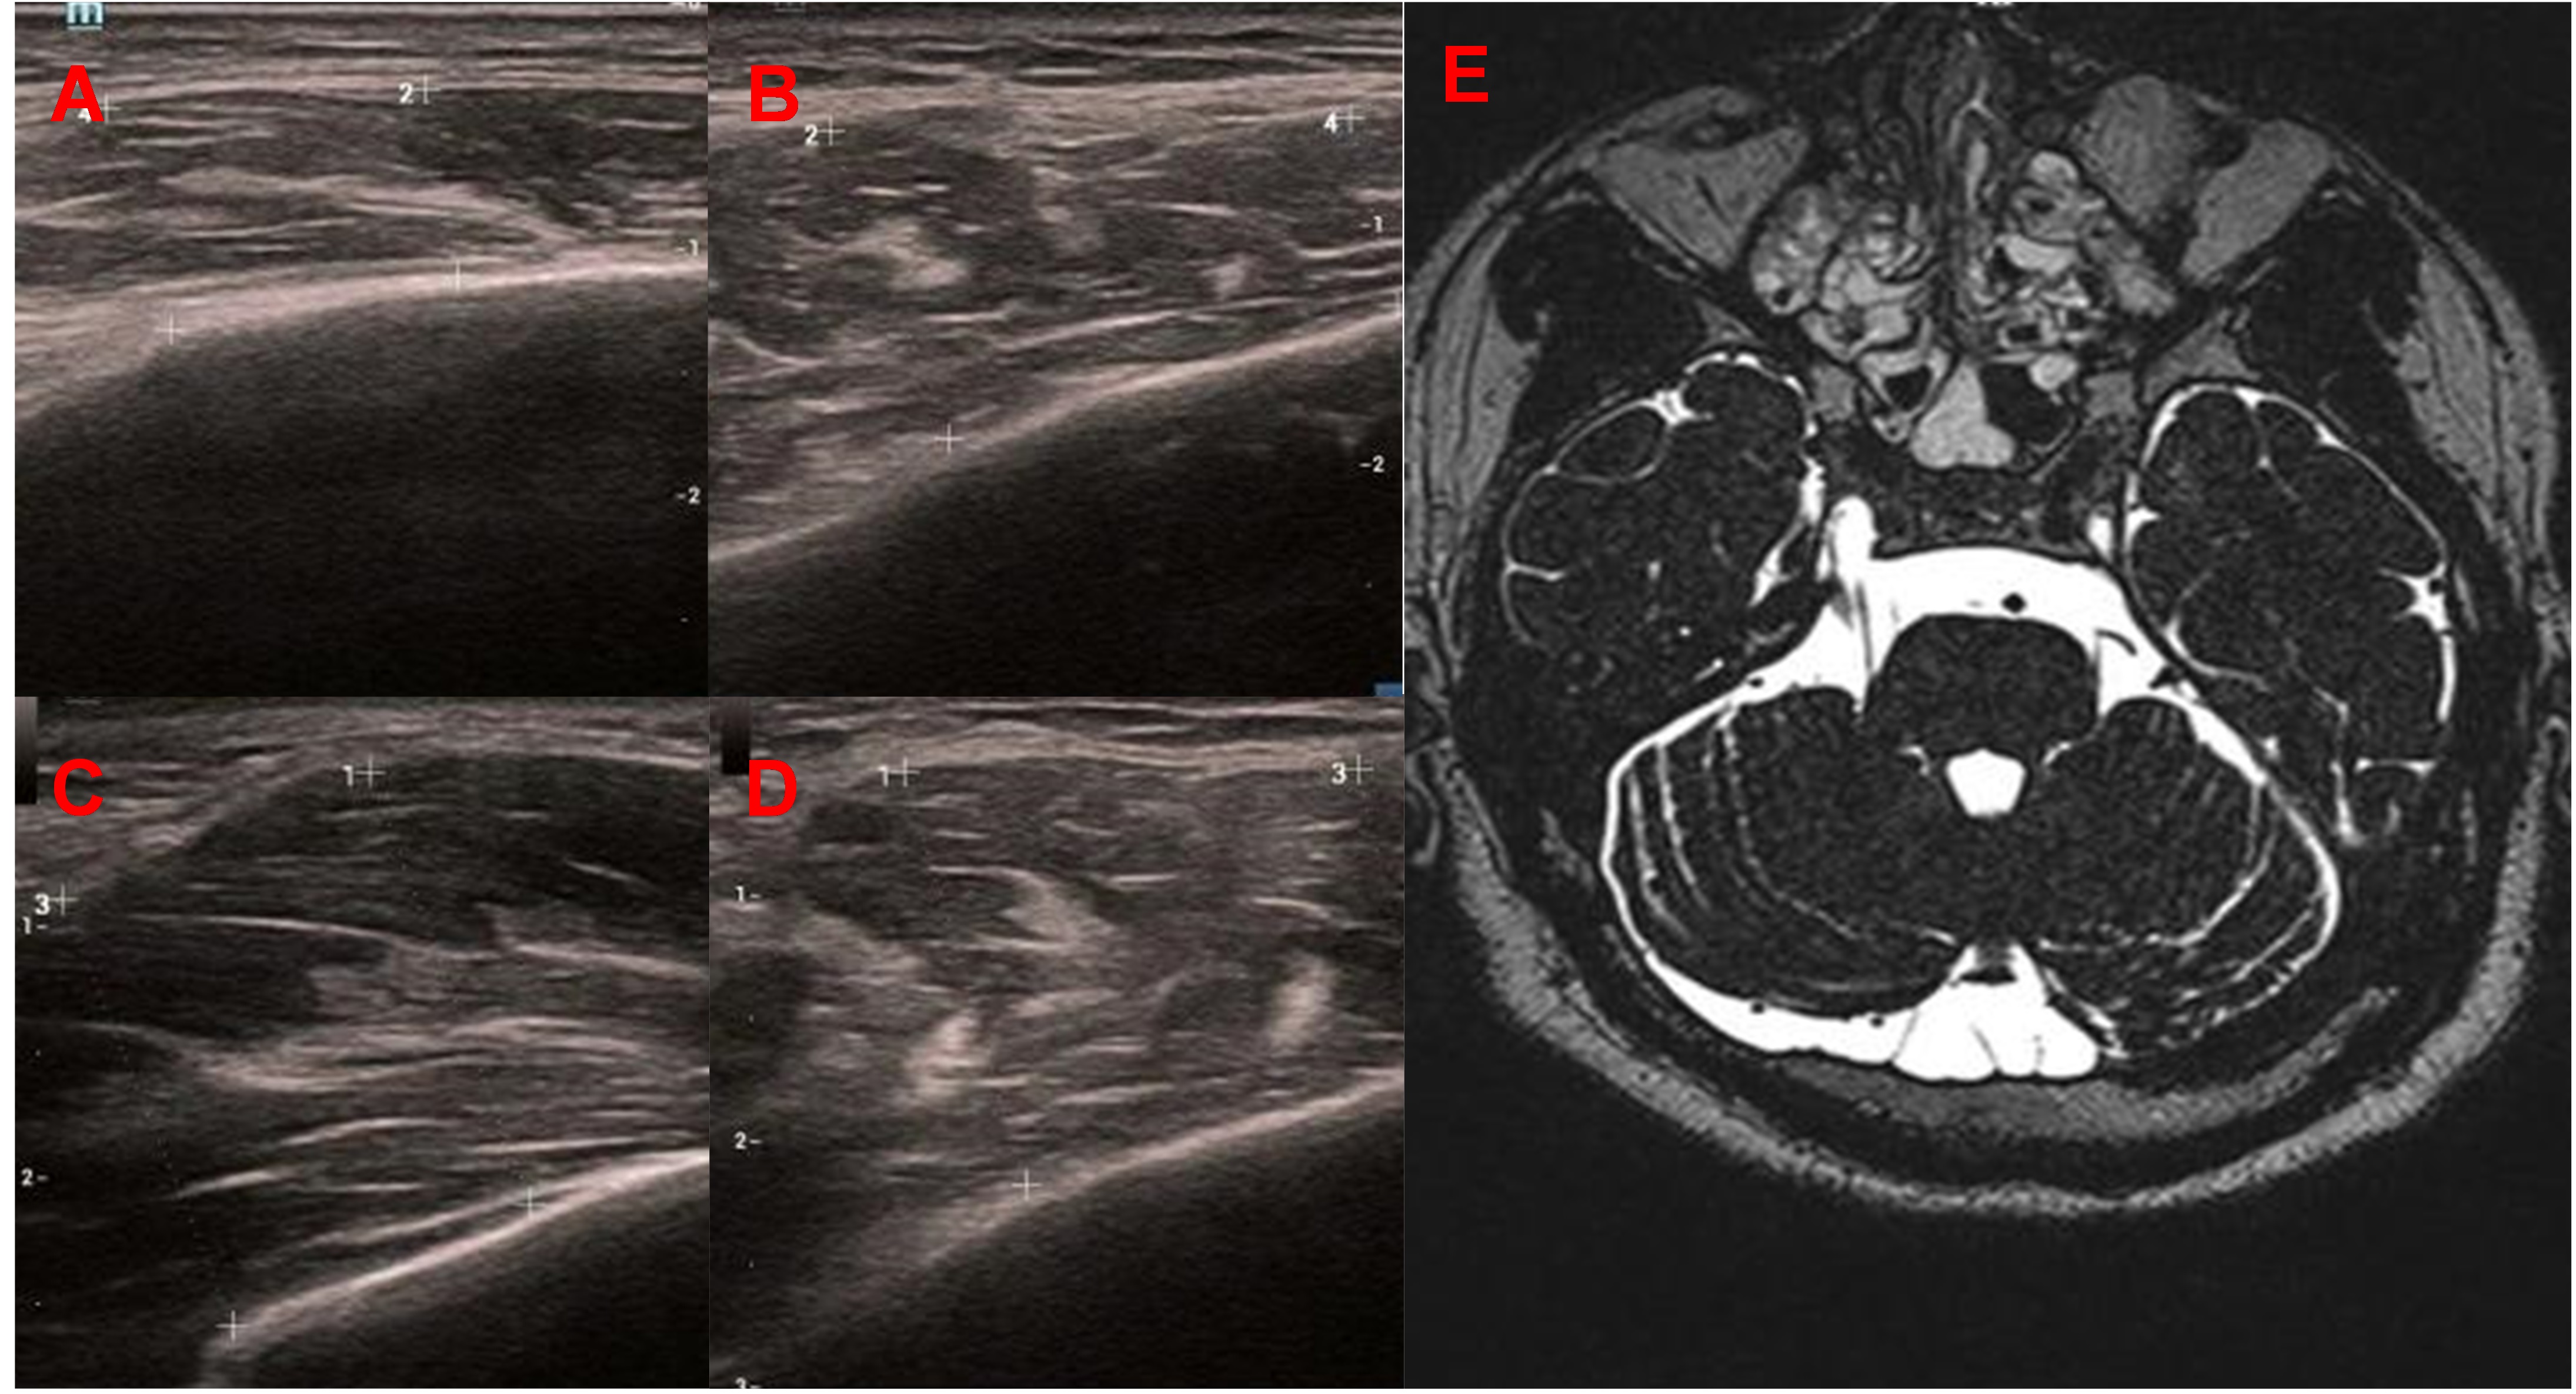

A 34-year-old man presented with a 4-year history of involuntary contractions of the left jaw and difficulty in mouth-opening. On physical examination, the left masseter muscle appeared normal in size. However, when the patient was asked to clench his teeth, involuntary contraction of the left masseter was observed. On Doppler ultrasonography, the left masseter muscle appeared normal at rest (8.4 mm vs 10.9 mm, Fig. 2A and 2B) ; however, it considerably increased in muscle thickness during contraction (18.3 mm, Fig. 2C), particularly when compared with the right side (14.6mm, Fig. 2D). MRI of the brain showed vascular compression of the left trigeminal nerve (Fig. 2E). The patient was injected with botulinum toxin A (50 U) into the left masseter. One month after treatment, he reported significant relief from the spasms without residual discomfort.

Fig. 2 Case 2.